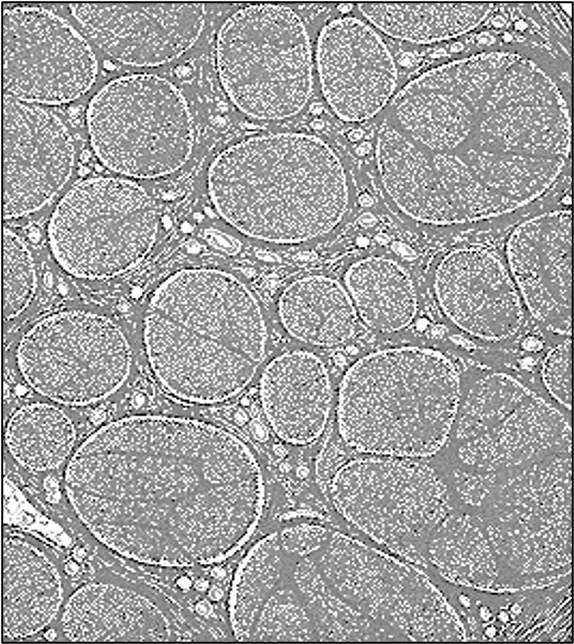

Individual nerve cells are supported by Schwann cells, which may encircle the nerve cell with a layer of fatty tissue called the myelin sheath

Myelination functions to insulate the nerve cell and improve transmission speeds (leading to faster signalling)

However, myelinated fibres require more space and have increased energy requirements, meaning some fibres may remain unmyelinated